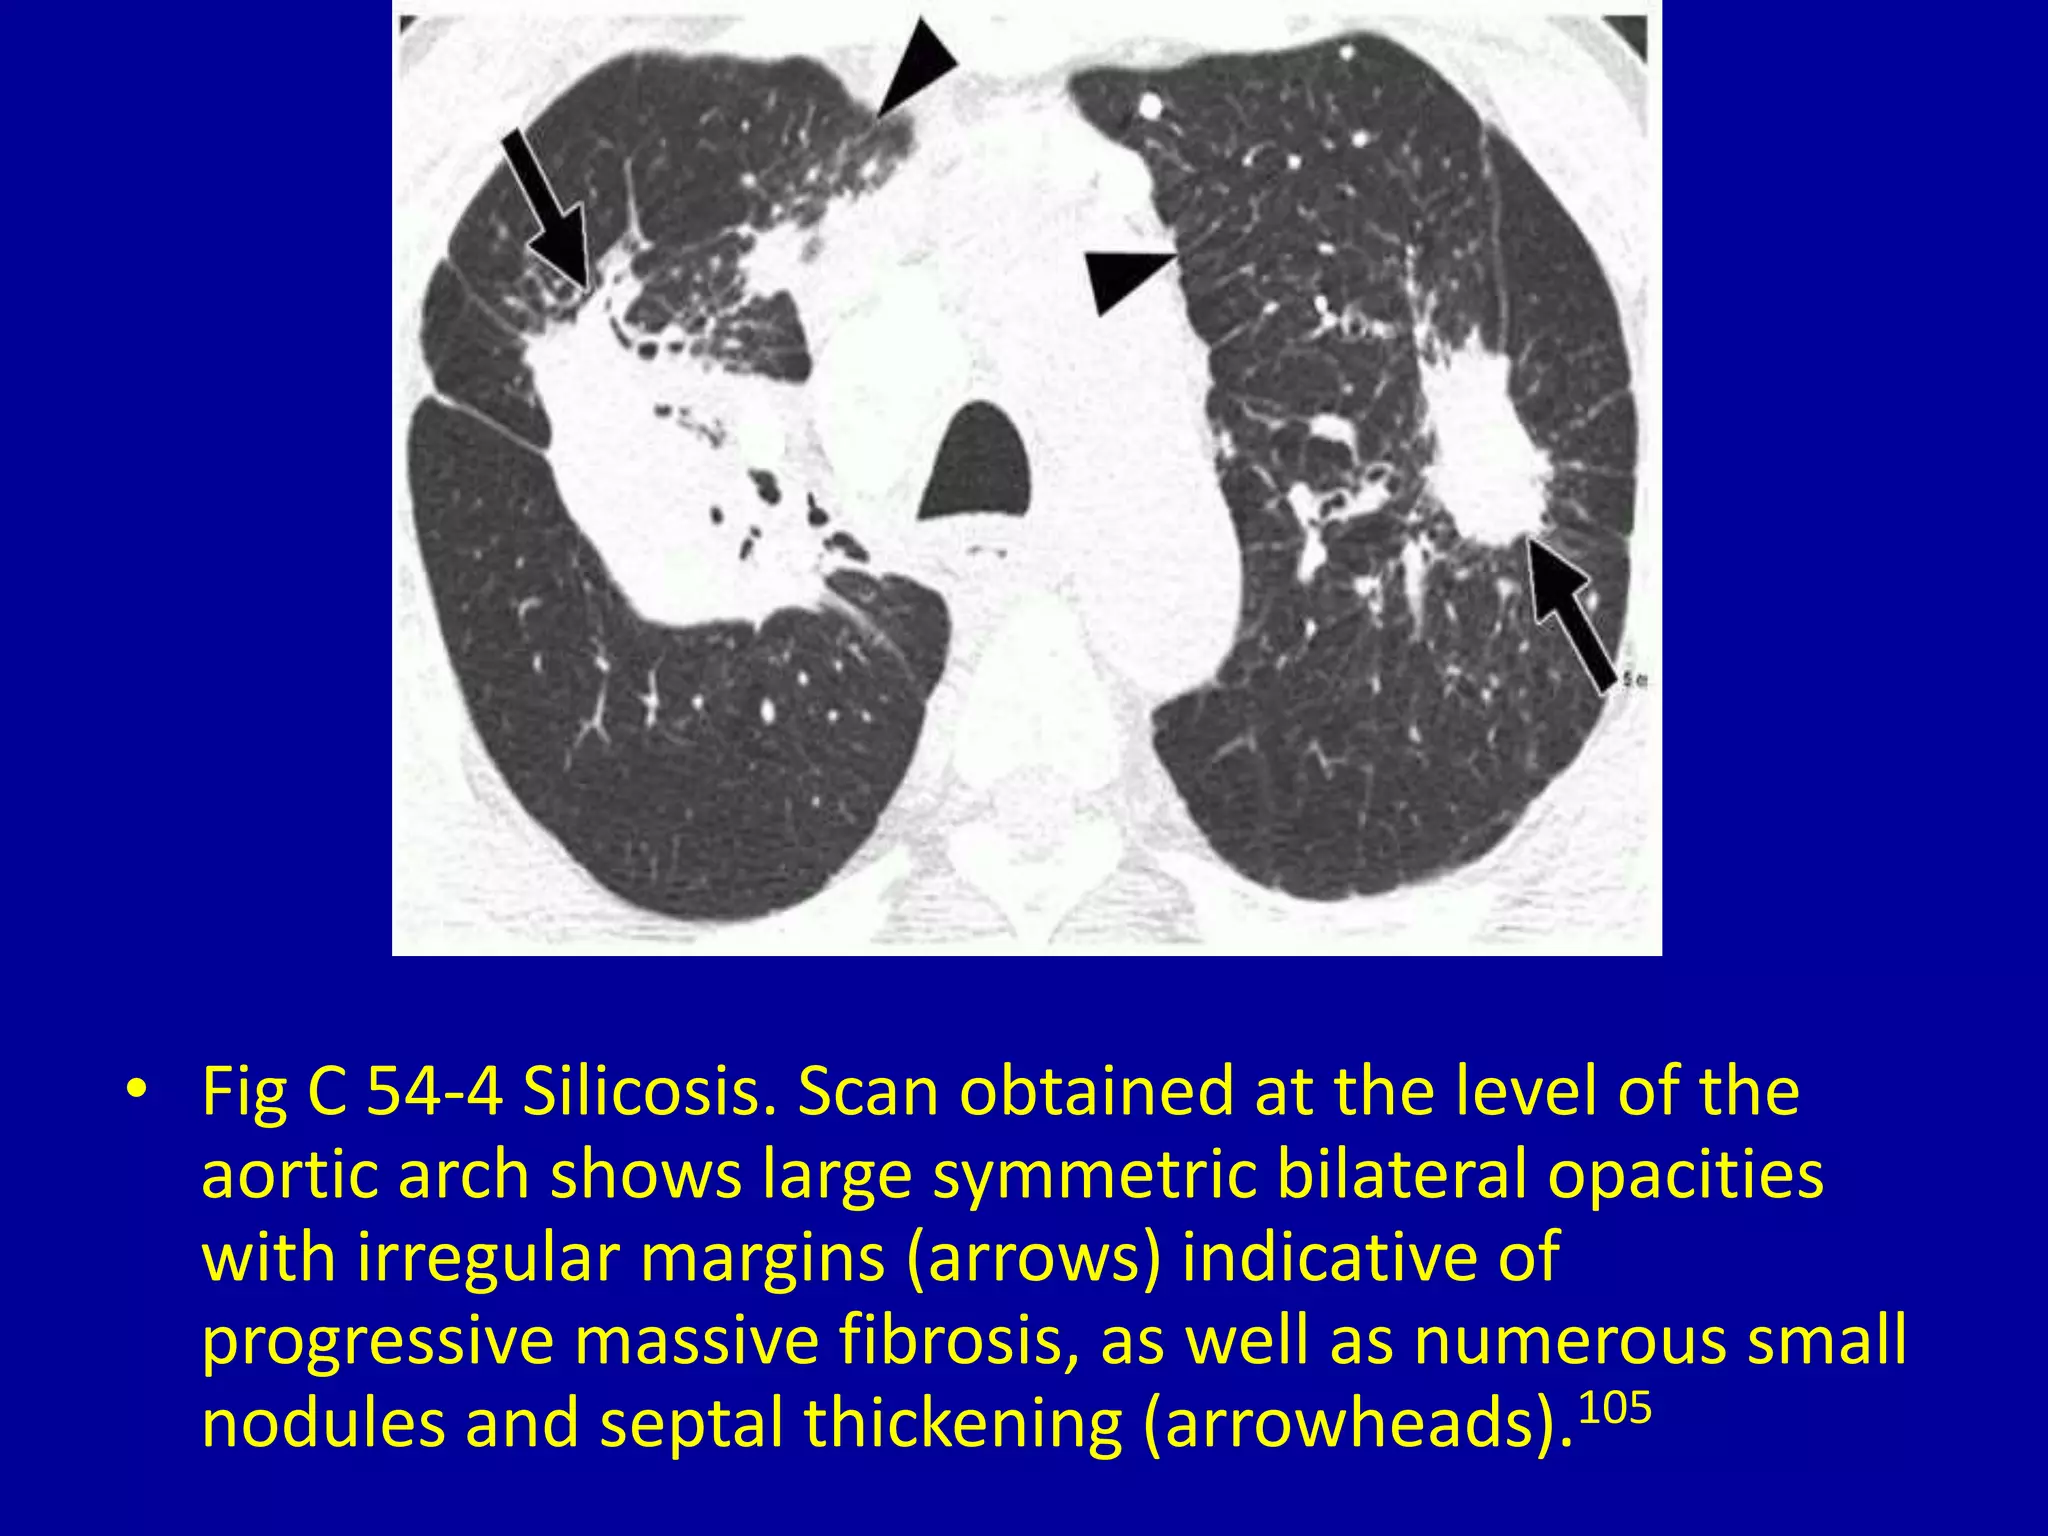

This document discusses various pulmonary diseases that predominantly affect the upper zones of the lungs. It includes 10 figures showing CT scan findings of different conditions like postprimary tuberculosis, sarcoidosis, pulmonary Langerhans cell histiocytosis, silicosis, centrilobular emphysema, chronic eosinophilic pneumonia, cystic fibrosis, allergic bronchopulmonary aspergillosis, neurogenic pulmonary edema, and ankylosing spondylitis. The images demonstrate lesions, nodules, consolidations, cysts, and other abnormalities that are largely limited to the upper lobes and regions of the lungs.